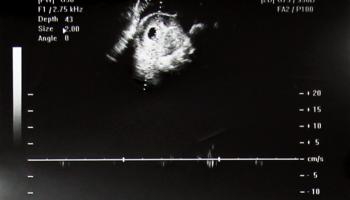

7. 임신 6주 차 - 연말이 예정일